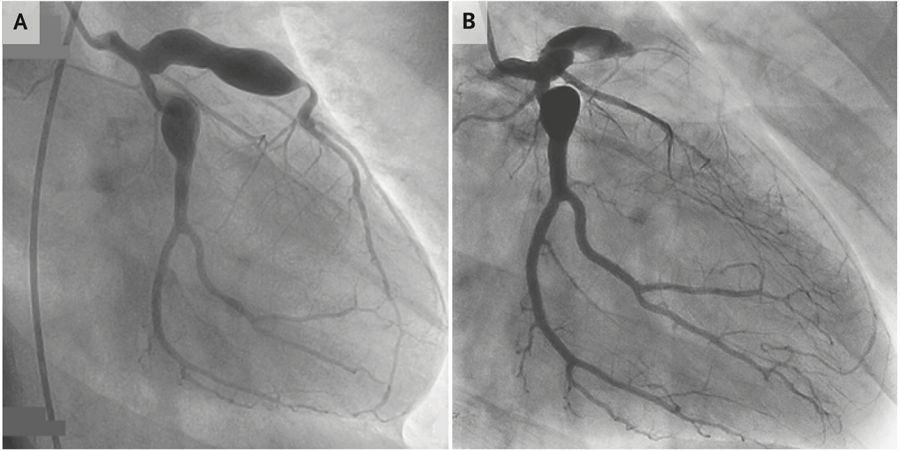

但这样的想法只持续了几分钟,因为患者的心电图清楚地显示,V1-V4导联ST段抬高(图1),似乎在和所有人较真“怎么的,老子就是心肌梗死”。再NB的概率也抵不过活生生的ST段抬高啊,于是只能乖乖地给患者安排冠脉造影,让人意外的是,“勉强的冠脉造影”提示前降支闭塞(图2)。什么鬼?真的18岁得了心肌梗死!

图2 冠脉造影提示多发瘤样扩张,前降支近端闭塞

仔细去看患者冠脉造影的结果,除了前降支的闭塞外,还存在着多发的瘤样扩张。毕竟是18岁的心肌梗死,必然有其特殊原因,于是重新仔细采集患者的病史:有没有经常熬夜?有没有高血压?有没有糖尿病?有没有家族性高胆固醇血症?答案统统是否定的。

虽然本病最显眼的体征在于皮肤、粘膜和淋巴结,但其最大的危害来自于“看不见”的并发症,包括心血管系统并发症、休克、巨噬细胞活化综合征等。尤其是心血管并发症,未经治疗的患儿发生率达20%~25%,而在心血管并发症中,冠脉瘤样扩张就是常见的一种。瘤样扩张的冠脉,在内皮损伤、血流缓慢等因素作用下,极容易形成血栓,血栓脱落流向远端,阻塞冠脉,造成心肌梗死。